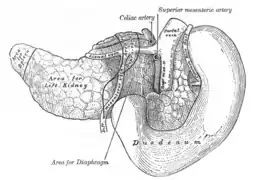

Tronco celíaco con sus ramas. (Lienal es un término antiguo para referirse a la arteria esplénica). El estómago está levantado e invertido. Compárese con la imagen anterior. | ||

Arteria hepática común

Se origina del tronco celiaco, se dirige hacia abajo, adelante y a la derecha por encima del páncreas, después de un trayecto de 4 cm. se divide en 2 ramas: la arteria gastroduodenal y la hepática propia. En su origen la arteria toma contacto con el borde superior del páncreas, cruza el pilar derecho del diafragma, luego se sitúa en el piso del vestíbulo de la transcavidad de los epiplones. En su trayecto de atrás hacia delante, levanta el peritoneo y forma el pliegue hepatopancreático. Posterior a esto la arteria hepática común se oculta tras la ampolla duodenal; se relaciona hacia arriba con el lóbulo caudado. Está rodeada por un plexo nervioso grueso emanado del plexo celiaco así como de vías linfáticas..tiene cuatro ramas colaterales:

- Pancreáticas. - Duodenales superiores. - Para los ganglios linfáticos escalonados. - Peritoneales y para el epiplón menor.

En sus ramas terminales se encuentra:

- Arteria gastroduodenal: se dirige hacia abajo y adelante, pasa en la porción superior del duodeno y de la cabeza del páncreas a la derecha del tubérculo omental. Delante de la cabeza del páncreas su origen marca la terminación de la arteria hepática común y el comienzo de la arteria hepática propia. Antes de ubicarse por debajo del duodeno la gastroduodenal proporciona la arteria pancreatoduodenal superior posterior. Se divide en dos ramas terminales:

A).- La arteria gastroepiploica derecha: se origina de la bifurcación de la arteria gastroduodenal que surge de la porción Terminal de la arteria hepática común, este origen se sitúa por debajo del borde inferior del duodeno en contacto con el páncreas, viaja inferior a la curvatura mayor del estómago y se anastomosa con la arteria gastroepiploica izquierda que viene de la arteria esplénica.

B).- La arteria pancreatoduodenal superior anterior.

- Arteria hepática propia: describe un codo cóncavo hacia arriba y hacia la izquierda que la sitúa en la raíz hepática, esta delante de la vena porta hepática, a la izquierda de la vía biliar principal, entre las dos hojas del epiplón menor. Es oblicua hacia arriba y a la derecha. Termina por la bifurcación en las arterias hepáticas izquierda y derecha. Sus ramas terminales son cuatro:

A).- Arteria gástrica derecha (pilórica): : originada de la arteria hepática propia, es oblicua hacia abajo y adelante, está situada en el epiplón menor el cual llega al borde superior del píloro en donde se divide en dos ramas terminales que siguen la curvatura menor. Ambas ascienden por esta al encuentro de las ramas correspondientes de la arteria gástrica izquierda. La acompañan vasos linfáticos y una vena supraepiploica, inconstante. La rama posterior de la arteria gástrica derecha se anastomosa con la rama posterior de la arteria gástrica izquierda, la anterior puede hacerlo o terminar en las ramas del estómago.

B).- Pequeñas ramas para la vía biliar principal. C.- La arteria cística, que se origina a menudo delante de la arteria hepática derecha. D.- Arterias para la cápsula fibrosa del hígado (red perihepática).

Sus ramas terminales penetran en el porta hepático, delante de la rama correspondiente de la vena porta hepática y se expande en el hígado, siguiendo las ramificaciones venosas. La rama más derecha es más voluminosa que la izquierda. Sus ramas arteriales son anatómicamente terminales.